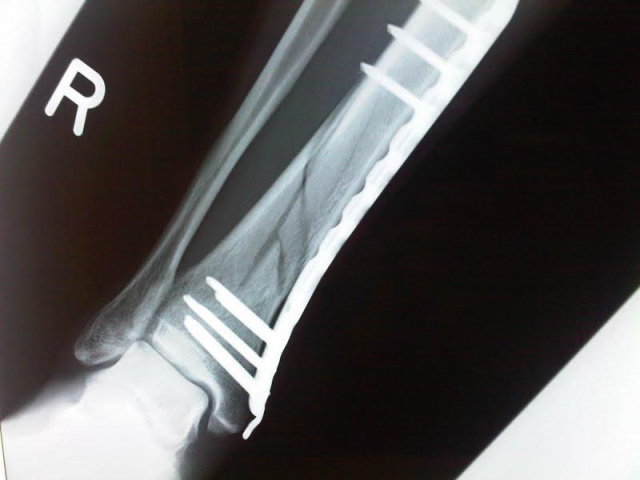

術後44日目

年のせいか、いまいち?

でも、骨膜形成はありそう。

なんて自分で診断しておりますが、次は11月15日(月)に外来があります。

まだまだ松葉杖での歩行であります!